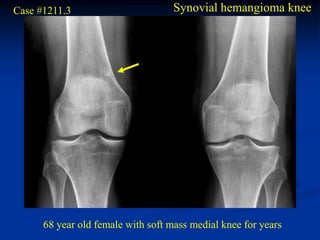

Case #1211.3                        Synovial hemangioma knee

68 year old female with soft mass medial knee for years

Cor T-1    T-2

Gad

Sag PD   Gad

Axial T-2   Gad